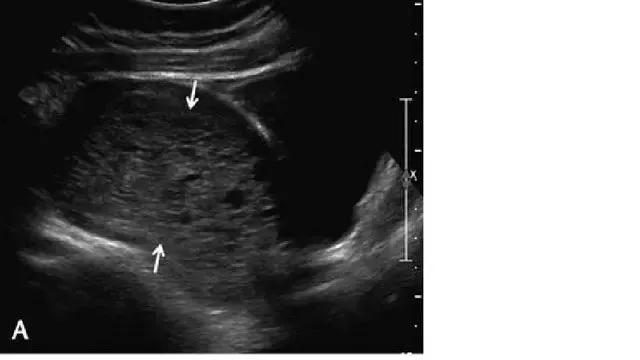

胎盘早剥

胎盘早剥指胎盘尚未成熟即与子宫壁分离开来的状况,是晚期妊娠出血的主要原因。胎盘前早剥发生于胎盘与羊水之间的绒毛膜板下,较其它类型的早剥少见;胎盘后血肿继发于蜕膜小动脉的破裂,导致血液在胎盘基底板与子宫壁之间积聚,可造成胎盘基底板坏死及绒毛梗死,导致严重不良妊娠结局。

此类出血的严重性与发生出血时的孕龄及血肿大小有关。早孕时出现较小的血肿,却可带来较大的影响。晚孕时的血肿若造成 50% 以上的胎盘与肌壁分离,则后果严重。

胎盘后复合体通常厚约 1~2 mm,由子宫胎盘血管及肌层所构成;如果超声发现此处增厚,应疑及胎盘后血肿。急性期的血肿回声较胎盘回增强或与之相同,一周后变为低回声,两周后可变为无回声(图 14)。

图 14 示胎盘早剥:A 为孕 24 周时的胎盘横切面,胎盘表面(长箭头)与羊膜(短箭头)之间可见一个较大的低回声区,此为胎盘前早剥。B 为孕 11 周的子宫矢状面,可见胎盘后的慢性无回声出血灶(长箭头),并延伸至绒毛下空间(短箭头),星号示出血灶导致胎盘边缘抬起。C 为另一孕 27 周伴无痛性阴道出血患者的子宫矢状面及横切面,长、短箭头所指回声为胎盘后的亚急性出血灶

超声对于急性或超急性胎盘早剥的检出并不敏感,尤其当出血灶局限于胎盘后方,此时胎盘外膜完整、出血灶处于隐蔽状态。胎盘后出血常常预示胎儿出生后的状况差,因而应积极处理这种出血。